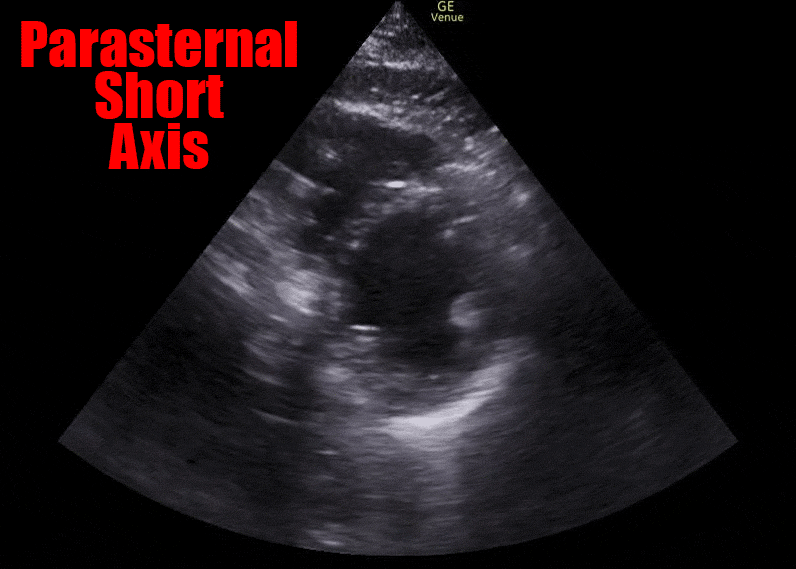

The following images (ECG and parasternal short axis view of the heart) were obtained on our patient immediately following ROSC.

The ECG shows ST segment elevation in the anterior leads, and the ultrasound shows an akinetic segment in the distribution of the LAD. This is the regional wall motion abnormality. The image below illustrates the finding. The heart cath confirmed a total occlusion of the LAD.